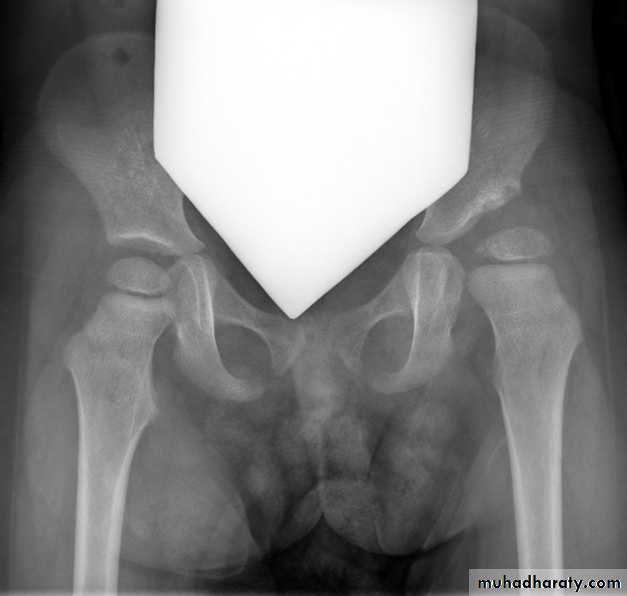

*Triradiate pelvis in which pelvic side walls bend inward (sever cases of osteomalasia )

Who can you do Von Rosen view

At 3-6 months :abduction of the thigh 45 degree and internal rotation

Shenton line is drawn along the inferior border of the superior pubic ramus and should continue laterally along the infero medial aspect of the proximal femur as a smooth line. If there is supero lateral migration of the proximal femur due to DDH then this line will be discontinuousPerkin line is drawn intersecting the lateral most aspect of the acetabuler roof & iliac creast

Q…CDH occurs most commonly in ????(70%) in the left hip . Bilateral involvement is seen in 5%

Q…By simple diagram draw pelvis with lines (shenton’s & Perkins line)